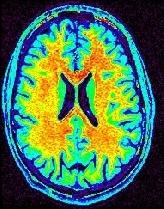

You may think that a unequivocal correspondence exists between the grey level in one voxel of a T1-weighted MR scan, and some esoteric property of the underlying cube of tissue. You should not succumb to this temptation. Take some time to observe a standard anatomical scan with a rainbow colormap to have this revelation:

Some parts of the white matter are red, while some others are yellow or even green. All looks like as if the putative correspondence mentioned above was depending on the localization in the field of view. Usually, the center of the coil is lighter, but this is not a systematic observation and depends on the coil and scanner design. When one looks at a MR slice with a grey colormap, like in standard radiology, this default is not straightforward. Human vision, indeed, is very effective at correcting for this kind of spatial variations. This capacity has some link with the fact that we usually perceive object's colors as uniform, whatever illumination related variations. Unfortunately, this sophisticated feature of human vision has prevented the MR physicists to find the motivation to overcome that acquisition problem. Artificial vision still being in its infancy, it is much more disturbed by these spatial intensity variations than radiologists. This procedure has to correct for the spatial bias before any segmentation process can be reliably trigered.